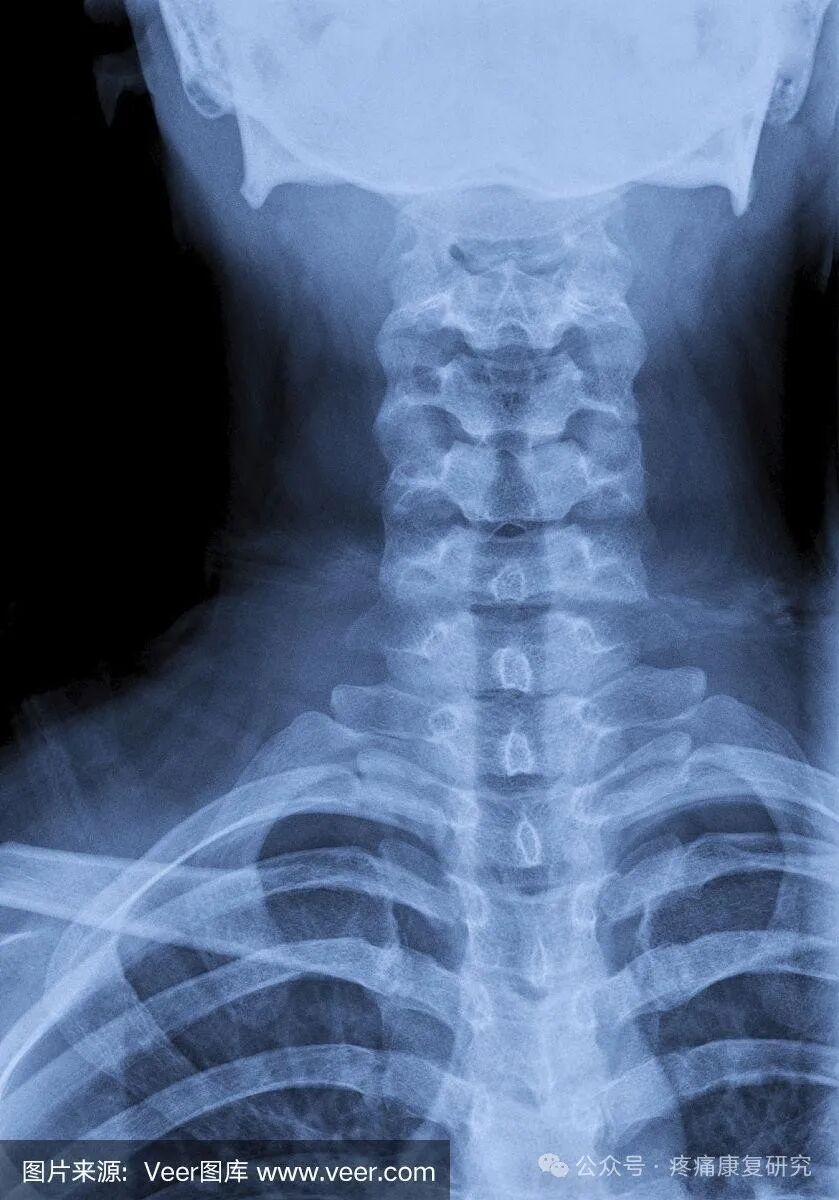

颈性眩晕

颈椎病的诊断需要结合患者的病史、症状、体格检查和影像学检查。医生可能会询问患者关于颈部疼痛、活动受限和头晕等症状的情况。

此外,还需要进行颈部X光、CT或MRI等影像学检查以评估颈椎结构的变化和压迫情况。